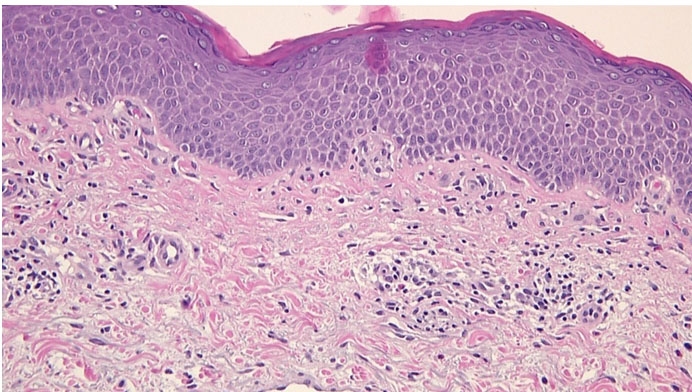

Core biopsy of the lung mass was performed on 18 March 2019. The features were suggestive of an infiltrating carcinoma in sheets with hyperchromatic nuclei. This was associated with brisk mitotic activity and scant or absent cytoplasm. No glandular or squamous components were seen, and the chromatin pattern also showed neuroendocrine features (Figure 2). Moderate nuclear positivity was seen with thyroid transcription factor 1 (TTF-1), but synaptophysin and chromogranin were negative. The diagnosis of small cell lung cancer was made based on the microscopic features and initial immunostaining. TTF-1 was positive along with focal staining of C56 and CAM 5.2 was also strongly positive. As initial overall morphological and immunohistochemical features were considered to be consistent with small cell carcinoma, the patient was commenced on carboplatin and etoposide. Her Eastern Cooperative Oncology Group (ECOG) performance score was 2, and she had mild hemoptysis during the first few days of the first cycle of chemotherapy. No significant improvement was noted in her symptoms after initiating chemotherapy. Interestingly, as the synaptophysin and chromogranin were negative, the immunohistochemistry (IHC) was extended with the additional stains, and those were strongly positive for P63 and CK5/6 (Figure 3). P63 and CK5/6 are usually negative in small cell carcinoma. Although there were features resembling small cell carcinoma in most areas, basaloid squamous cell carcinoma (BSCC) features were also noted on further review of the slides. Due to these findings, it favored the diagnosis of basaloid squamous cell lung carcinoma.

Figure 2: Core biopsy of lung: (Hematoxylin and Eosin stain) showing hyperchromatic nuclei with brisk mitotic activity, scant cytoplasm without any glandular or squamous component.